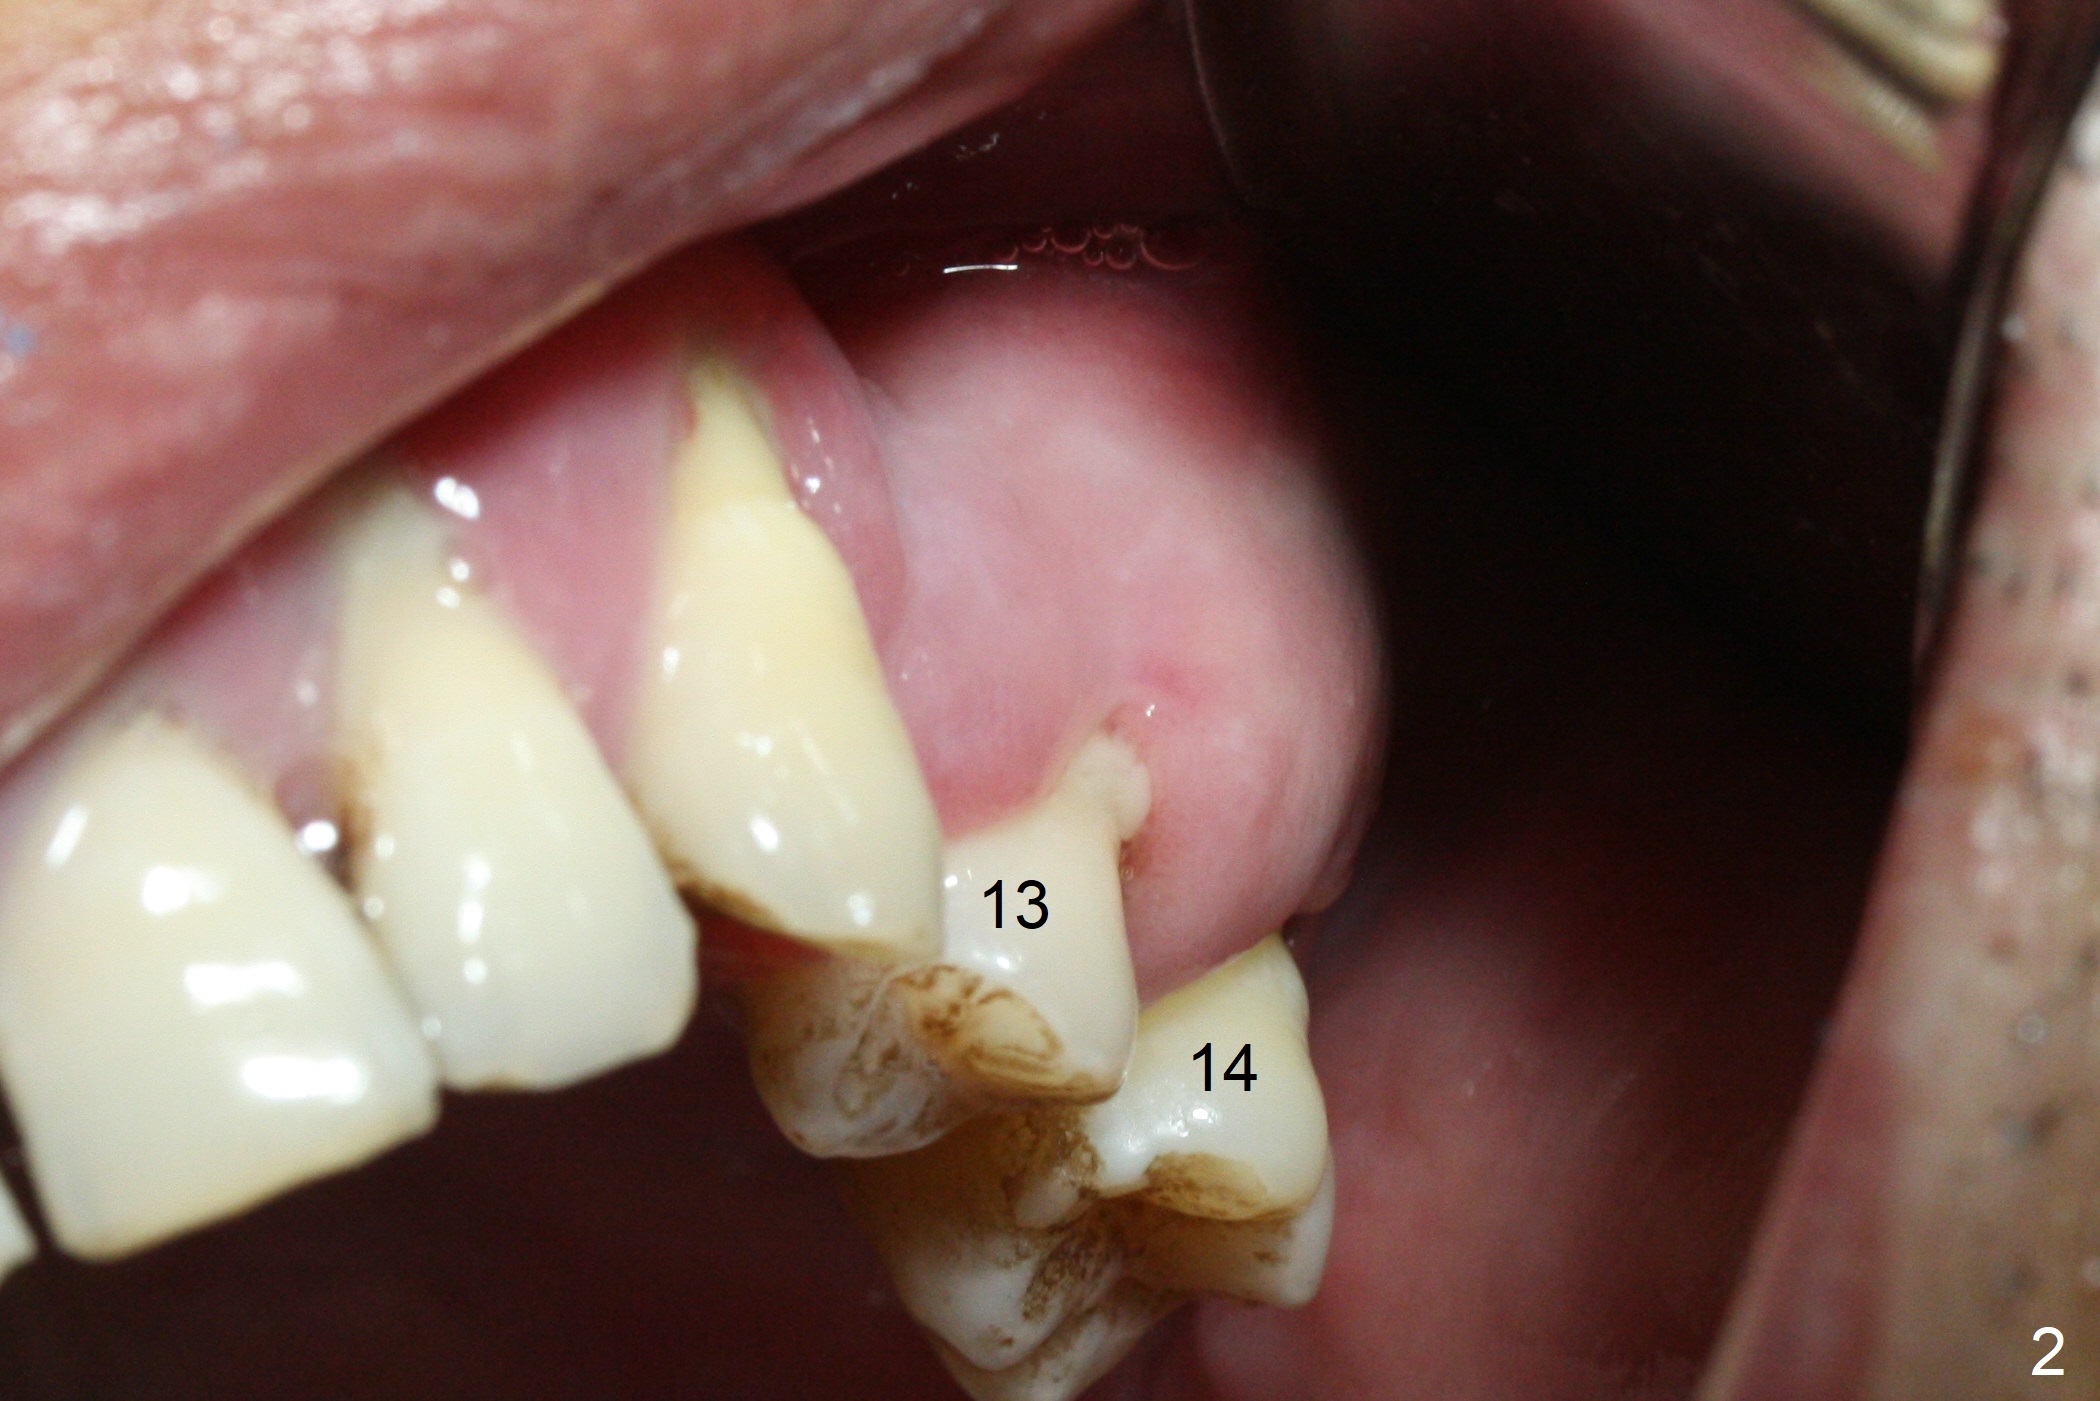

The 36-year-old man (ex-smoker, quit for 4-5 years) insists upon #3 and 5 extraction first for implants, in spite of more severe infection at #7, 14,19,30 (Fig.1-4). The gingiva around #23-26 implants is healthy 3 weeks postop (Fig.5). The initial depths at #3 and 5 are 8.5 mm (bone-level) and 18 mmm (gingiva-level (13 mm (implant length) + 5 mm cuff), respectively. When a drill penetrates the sinus floor, confirm the depth. After use of 3.8 mm drill, 4.5 mm tap drill is inserted at #3 without stability, while a 4.5x13 mm implant is placed at #5 with primary stability (Fig.6,7). Then a 5x11.5 mm is placed at #3 subcrestal proximally after sinus lift with Vanilla graft (without sinus membrane perforation; Fig.8). The implant at #5 is seated ~1 mm deeper (subcrestal mesially (^^); supracrestal distally (^)); allograft is placed around the implants prior to insertion of 6.5x7(5) and 5.5x4(5) mm abutments; last more allograft is added (Fig.9 *, 10). The implants seem to have been osteointegrated 4.5 months postop (Fig.11,12). The gingiva is healthy around the implants without bone loss 3 months post cementation (Fig.13,14).